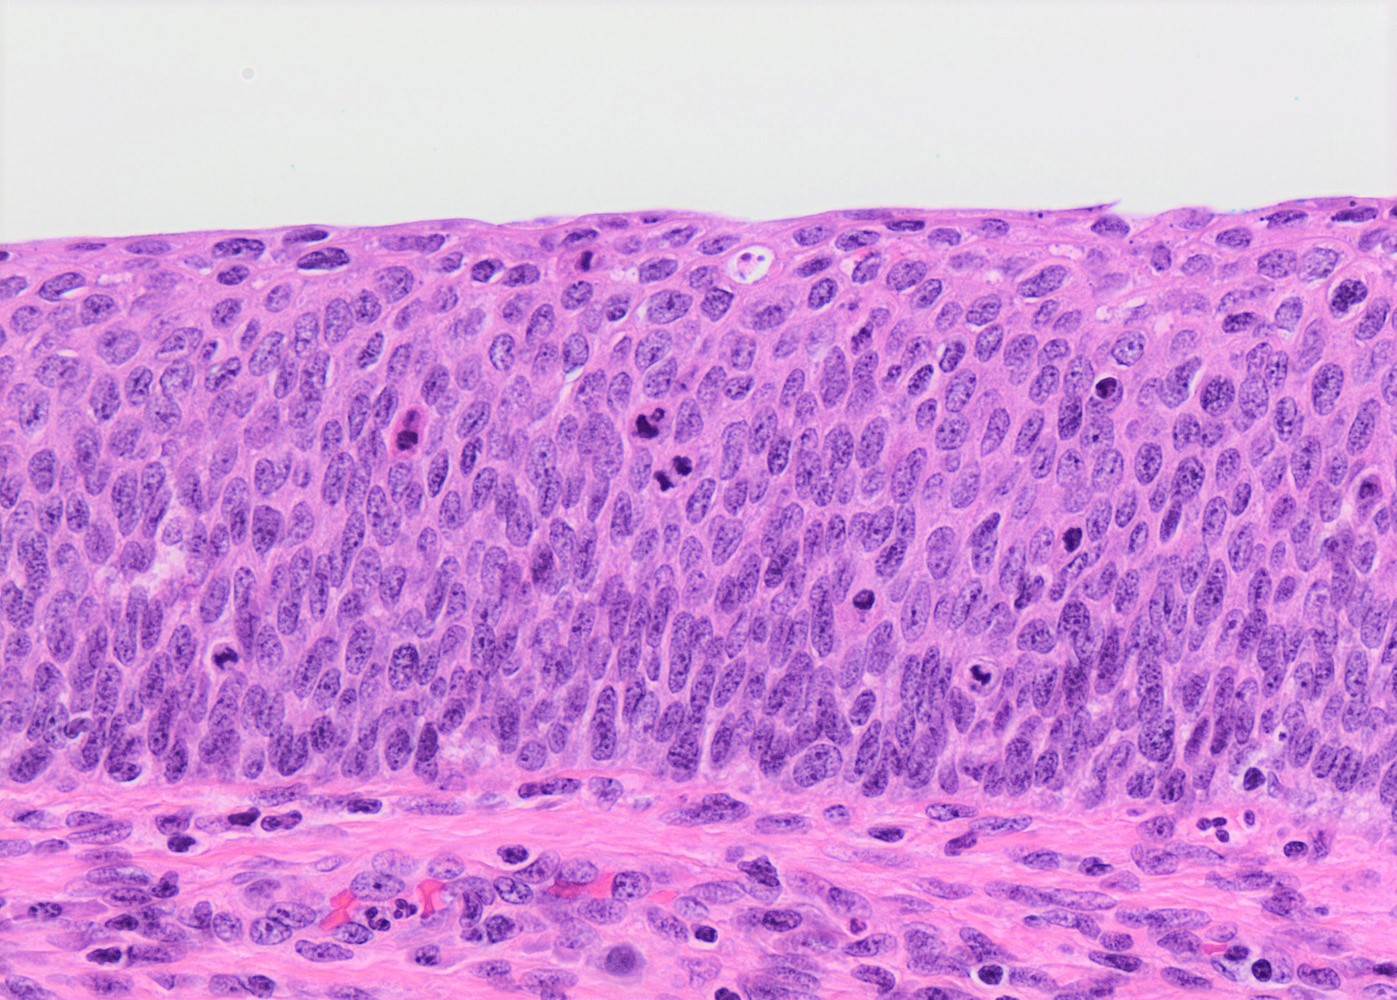

- Conventional / classic pattern: full thickness nuclear abnormalities (hyperchromasia, coarse chromatin, irregular nuclear contours and inconspicuous nucleoli), high N/C ratio in at least lower two - thirds of epithelium

- CIN III: full thickness basal / parabasal type, no maturation difference across layers

- Increased mitotic activity with atypical mitoses

Microscopic (histologic) images

Contributed by Khaled J. Alkhateeb, M.B.B.S.